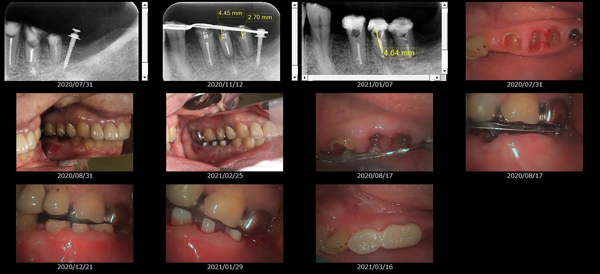

救歯MTM

虫歯が大きくて残せない歯、転倒などの事故により歯が根の深いとこで折れてしまったなどで、抜かざるを得ない歯を、骨の中に埋まっている健全な根を、骨の上に矯正的に引き上げることで、その歯を抜かず温存、救歯できる可能性のある治療方法です。

①健全な歯を、歯肉から見える位置にまで引き上げることで

根の治療の成功率を上げることが出来る。唾液には沢山の細菌がいます。唾液が入らない環境での根の治療を(神経の治療)を行うことで神経の治療、根の治療の成功率は格段と上がります。

②骨の上にある歯と土台で支える被せもの製作できる。

被せものを土台だけに頼ることなく、引き上げた健全な歯でも支えることで、歯への被せ物がしっかりと装着できるようになる。

③抜かずに歯を活かすことで、隣の歯を削るブリッジやインプラントにしないで済むことがある。

歯を矯正的に引き上げることで、その歯を救歯できるだけでなく、隣の歯を削るなどの侵襲を回避できる場合がある。

救歯治療と審美性の両立

当院では様々な治療の基礎に審美と機能の両立というテーマがあります。

- > 歯を矯正的に引き上げることで、骨の中の根の長さは短くなりますが、その短さでも安定するという診断をした場合のみ施術になります。 残せる歯、根の長さが短い場合は、この救歯MTMの治療対象とならない場合がございます。

- > 治療期間が数か月~1年に及ぶ場合がある。

- > 費用が自費診療 44,000円 ~ 66,000円

- > 救歯MTMは救歯BTAセラミックと併用治療が必要な場合があります。

症例